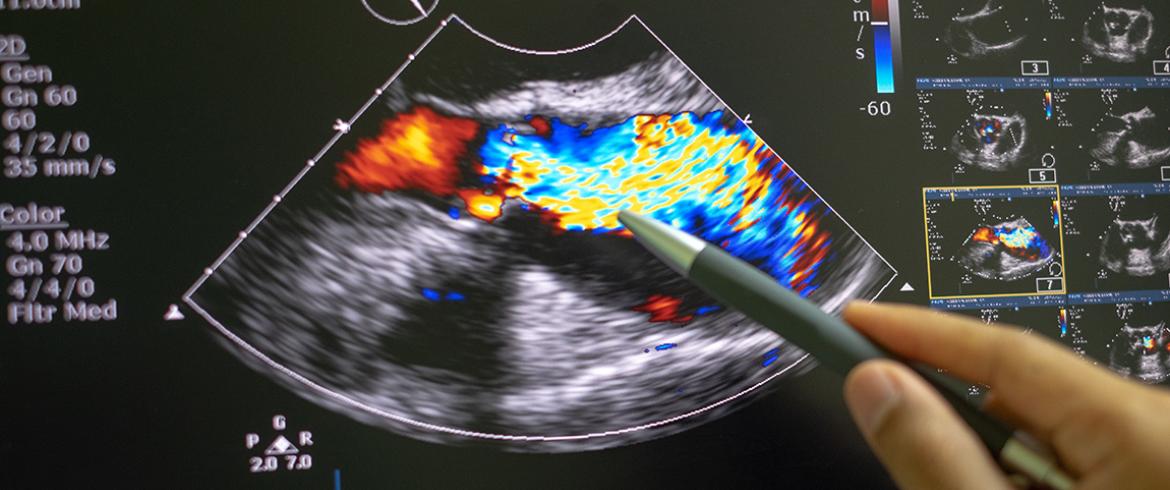

Ultrasound machines, in contrast, are widespread. De and his team will develop their technique with B-mode ultrasound, which is already widely used for monitoring pregnancies, echocardiogram scans of the heart and other common procedures. Portable devices that could be used at forward operating bases in the military use the same technology.